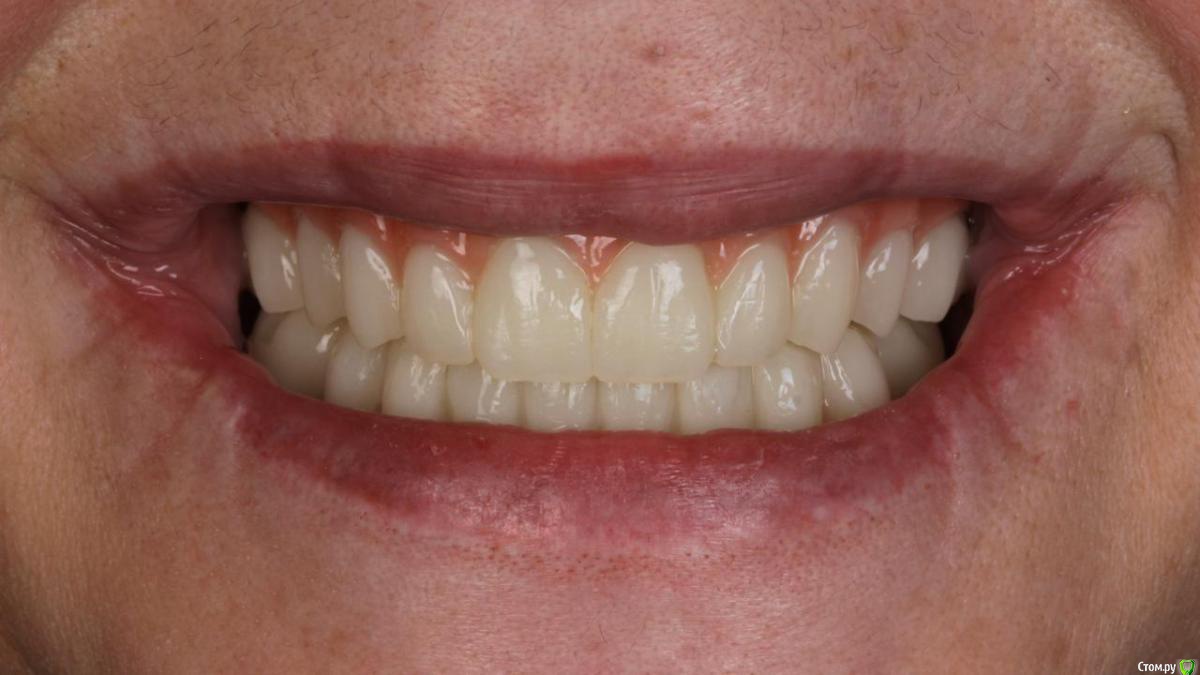

Bier Опубликовано 10 февраля, 2020 Поделиться Опубликовано 10 февраля, 2020 Хирургия в седации 3,5 часа + редукция гребня. По шаблону под пилот. Все мультиюниты были заранее выбраны техником и четко сели.Временные армированные протезы (лазерное спекание) 8 Ссылка на комментарий

Bier Опубликовано 11 февраля, 2020 Автор Поделиться Опубликовано 11 февраля, 2020 А какую финальную конструкцию планируете?Металло композит или металлический каркас с индивидуальными коронками из керамики. Скорее всего на одну челюсть так, другую так. Ссылка на комментарий